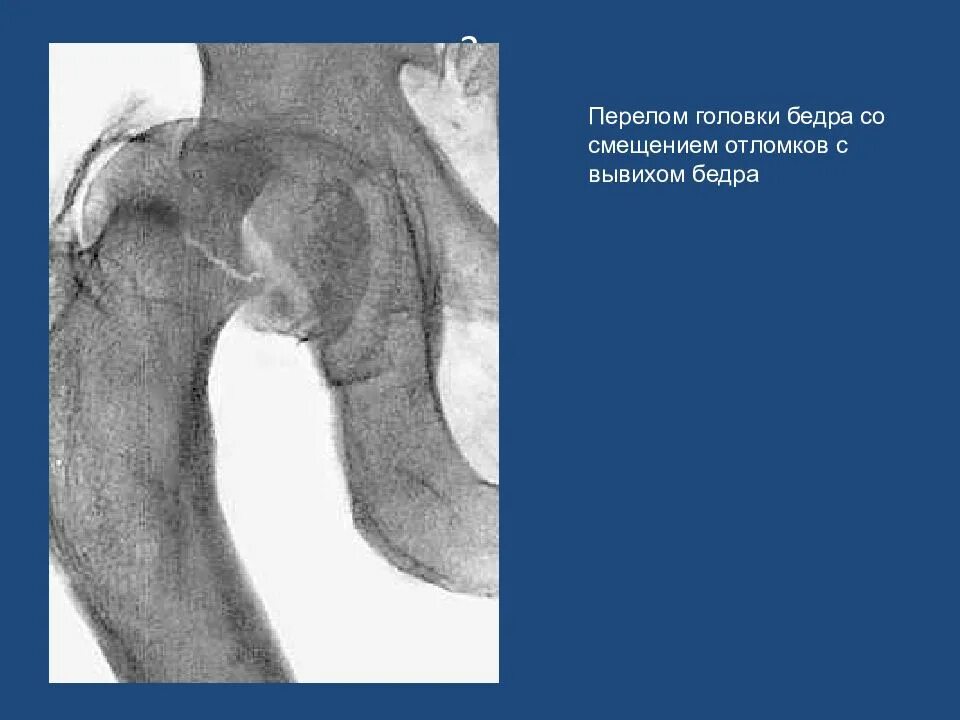

Вывих со смещением